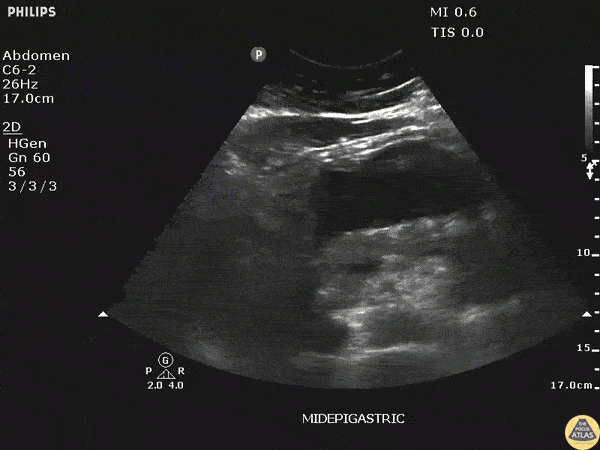

An elderly male with abdominal pain, hypotension and a palpable abdominal mass. POCUS revealed a normal sized pulsatile aorta with a large pancreatic pseudocyst. Image courtesy of Robert Jones DO, FACEP @RJonesSonoEM Director, Emergency Ultrasound; MetroHealth Medical Center; Professor, Case Western Reserve Medical School, Cleveland, OH View his original post here